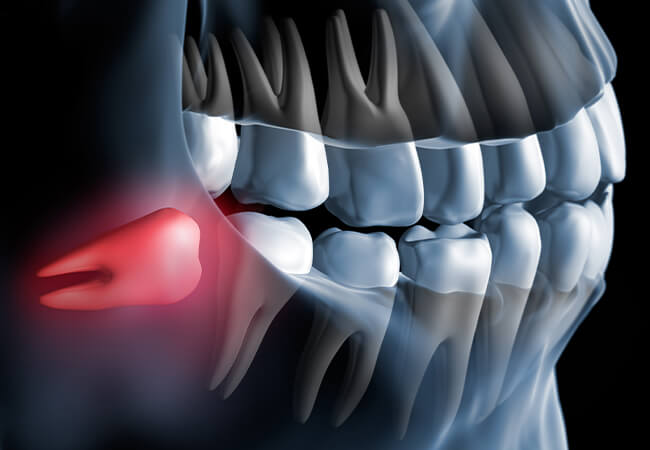

親知らずの痛みや違和感は、炎症やむし歯が原因の場合があります。

*考えられる疾患

智歯周囲炎、親知らずのむし歯、隣在歯への影響。